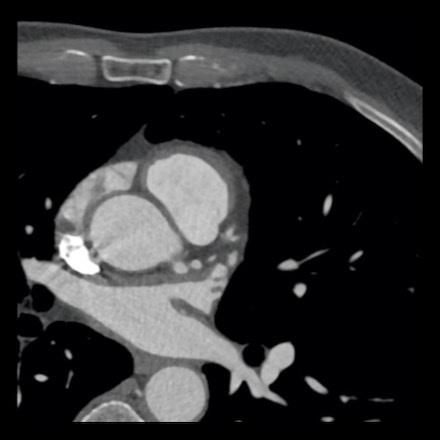

case 2 – CAD-RADS 5/P2/S

First, scroll through the CTA images.

How would you describe the findings on the coronary CTA?

The findings are:

- Stent in the mid

LAD with low-attenuation within the stent suggestive of minimal in-stent

restenosis (<25%). Non-calcified plaque distal to the stent

causing mild stenosis (25-49%). Notice bridging on a short segment in

the distal LAD. - Non-calcified

plaque in the LCX causing mild stenosis (25-49%). - Occlusion of the

proximal OM1 branch with distal filling. - Calcified and

non-calcified plaques in the proximal RCA causing mild (25-49%) stenosis. - Total plaque burden

is moderate based on SIS (four segments including proximal RCA, mid LAD, prox

LCX and OM1).

Due to the occlusion of OM1 branch and presence of the stent, this case

reads as CAD-RADS 5/P2/S, which means that this patient needs further

diagnostic workup.